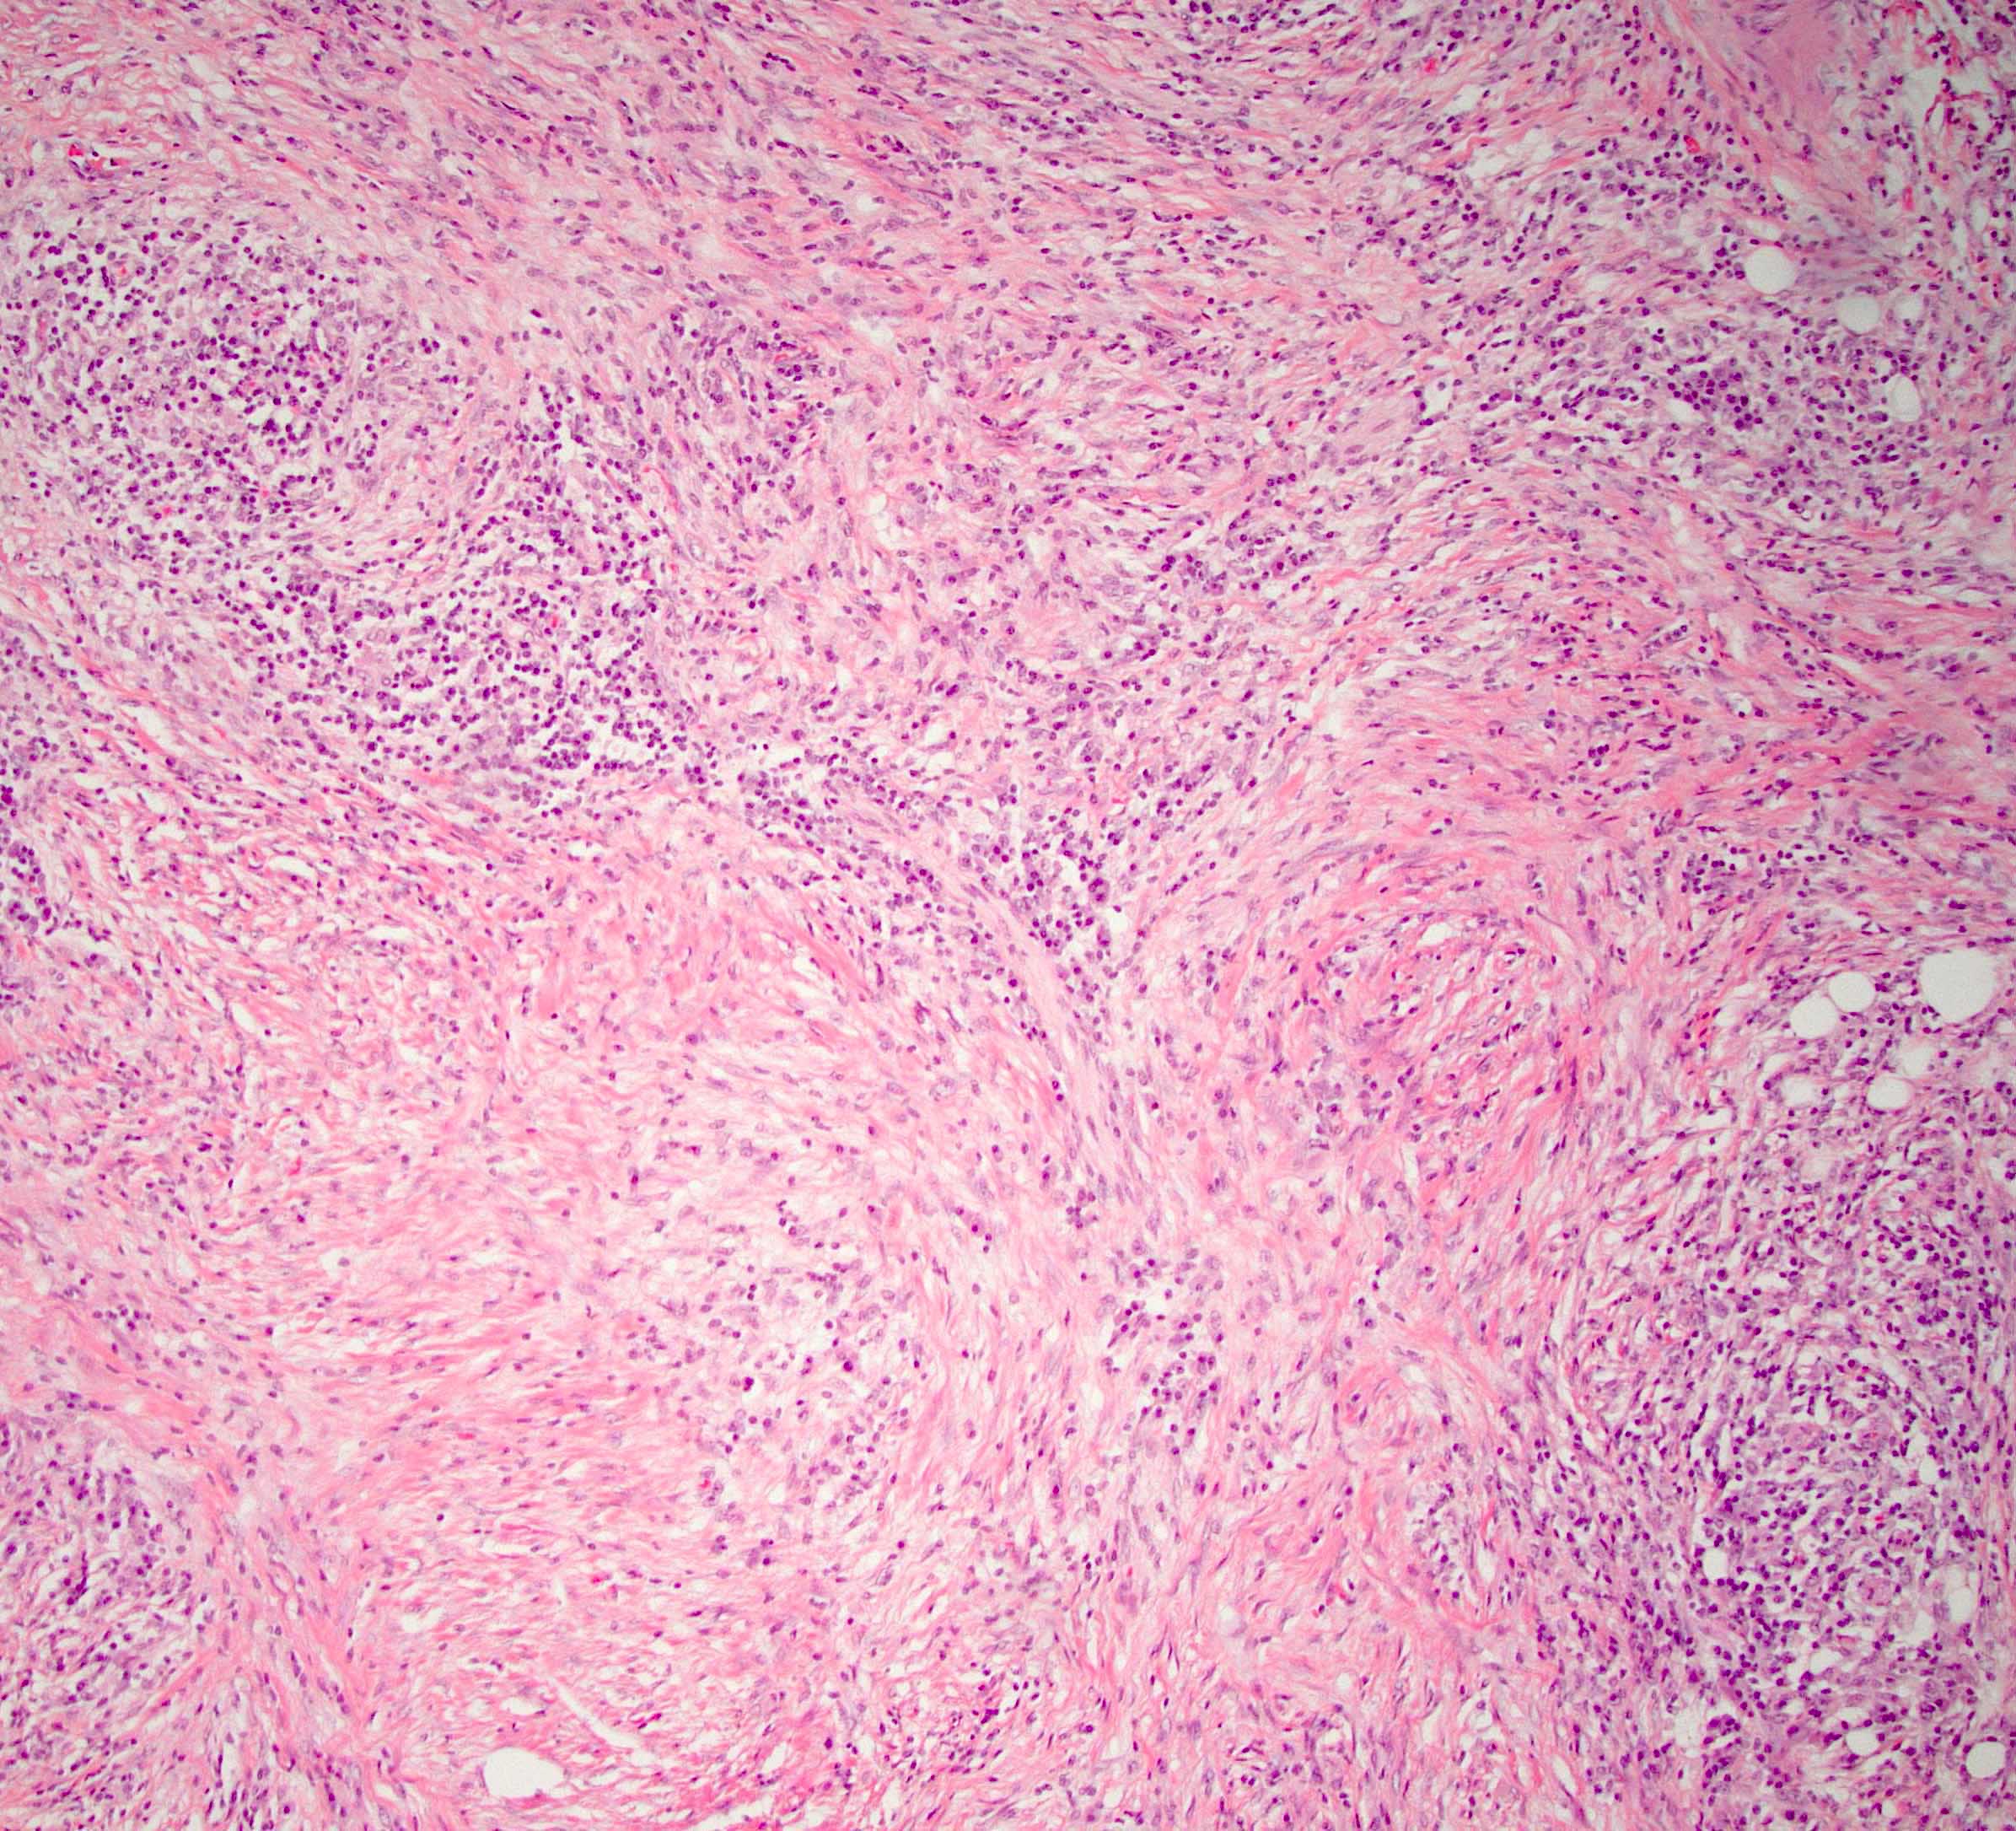

Microscopic (histologic) description

- Characteristic findings (at least 3 for level 1 criteria) (Pancreas 2011;40:352)

- Periductal lymphoplasmacytic infiltrate without granulocytic infiltration

- Obliterative phlebitis

- Storiform fibrosis

- Abundant (> 10 cells/high power field) IgG4 positive plasma cells

- Biopsy showing some but not all of the above features can be used as supportive evidence for the diagnosis of autoimmune pancreatitis (Pancreas 2011;40:352)

- Inflammation is localized within the pancreatic parenchyma and is centered around / within medium to large interlobular ducts, which causes shrinkage of the ductal lumen (Pathologica 2020;112:197)

- Inflammation can also be seen between the pancreatic parenchyma and peripancreatic adipose tissue (Pathologica 2020;112:197)

- Inflammation of the venous wall can progress to obliterative phlebitis with fibrosis of the lumen (Pathologica 2020;112:197)

- As the inflammation progresses, fibrosis becomes more diffuse, assuming a whorled or storiform pattern (Pathologica 2020;112:197)

- Perineural inflammation can also be present (Pathologica 2020;112:197)

Microscopic (histologic) images

C. Elevated IgG4 on serology. The histologic section shows the characteristic findings of autoimmune pancreatitis (AIP) type 1 (storiform fibrosis and a lymphoplasmacytic infiltrate). Most AIP type 1 patients have elevated IgG4 on serology. Answer A is incorrect because patients do not present with symptoms of acute pancreatitis (acute abdominal pain with elevated lipase on serology). Answer B is incorrect because AIP type 1 patients can present with elevated CA 19-9 on serology but this is not as common as elevated IgG4. Answer D is incorrect because inflammatory bowel disease is associated with AIP type 2, not type 1. Answer E is incorrect because a pancreas mass can be seen in AIP type 1 but this is variable.